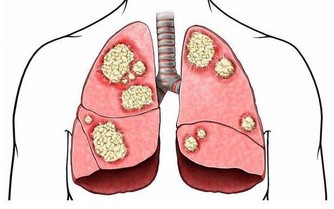

中醫認為,凡致病具有重著、黏膩、趨下特性的外邪,都稱之為濕邪。中醫將濕邪分為外濕和內濕兩種。外濕多因環境潮濕、涉水淋雨所致,內濕多由過食生冷而致脾陽受損。外濕可內傳臟腑,內濕也可外達肌膚,濕邪又易與風、寒、暑、熱等邪氣相互糾結,稱為風濕、寒濕、濕熱、暑濕等。